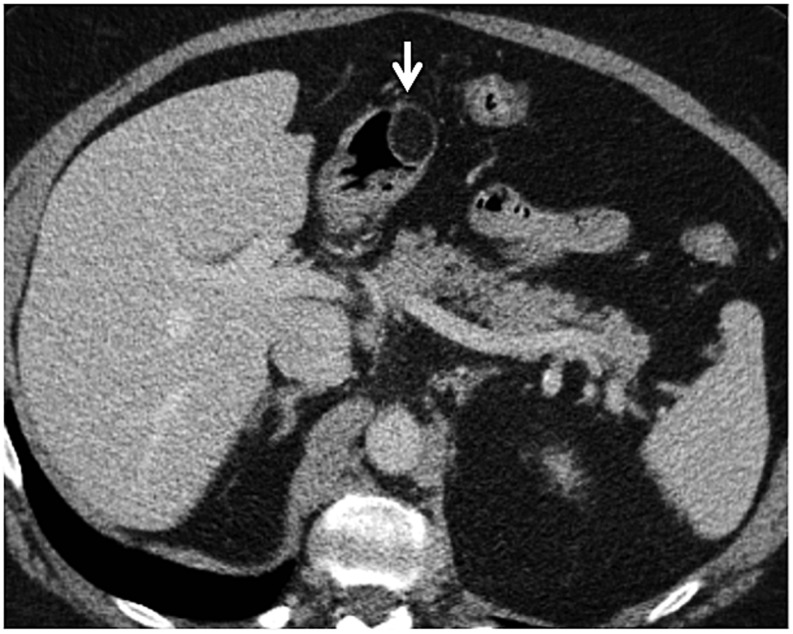

The appearance on CT may be non-specific and common patterns include diffuse wall thickening, polypoidal mass, thickened folds or infiltrating lesions (Figure 6a). The common differential includes gastric cancer. CT features that favour gastric lymphoma include preserved gastric distensibility despite diffuse wall infiltration, involvement of more than one segment of the stomach, the presence of perigastric lymphadenopathy, greater wall thickening, preservation of fat planes with adjacent organs, transpyloric spread and the presence of lymphadenopathy below the renal hilum.7,26,27 To best of our knowledge, there has been no study to show the appearance of gastric lymphoma on VE; however, we found it helpful in our limited experience. Ulcerative gastric lymphoma or polypoidal lymphoma is well seen with VE. With VE, gastric distension is assessed, which is preserved in lymphoma, helping it differentiate from adenocarcinoma in which gastric distensibility is decreased or lost. Also, when the disease is diffusely infiltrative, the presence of “nodular” thickening of the gastric folds may also point towards lymphoma as possible aetiology of fold thickening (Figure 6b). CT is the primary imaging modality for pre-treatment evaluation and staging.24 Fluorine-18-FDG PET-CT may be challenging in these patients, as a small lesion may be obscured by the physiological uptake of FDG in gastric mucosa. The variability of FDG uptake with different histological subtypes can sometimes make it difficult to interpret.28

Figure 6.

A 66-year-old female with abdominal pain, fever and weight loss: the axial (a) CT is showing diffuse thickening of the stomach (white arrows) with relatively preserved distensibility. The left renal cyst is incidentally noted (black arrow). The CT gastroscopy image (b) is showing diffuse nodular gastric fold thickening (open arrows) in this patient with non-Hodgkin lymphoma.